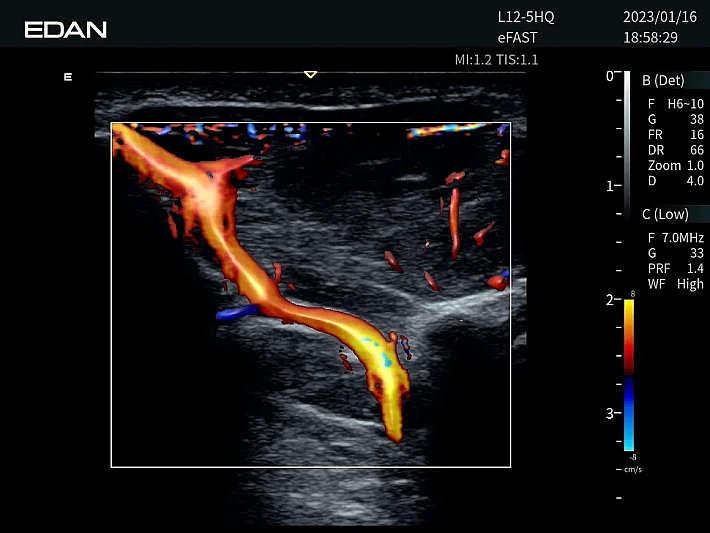

Медицинское оборудование и сервисное обслуживание